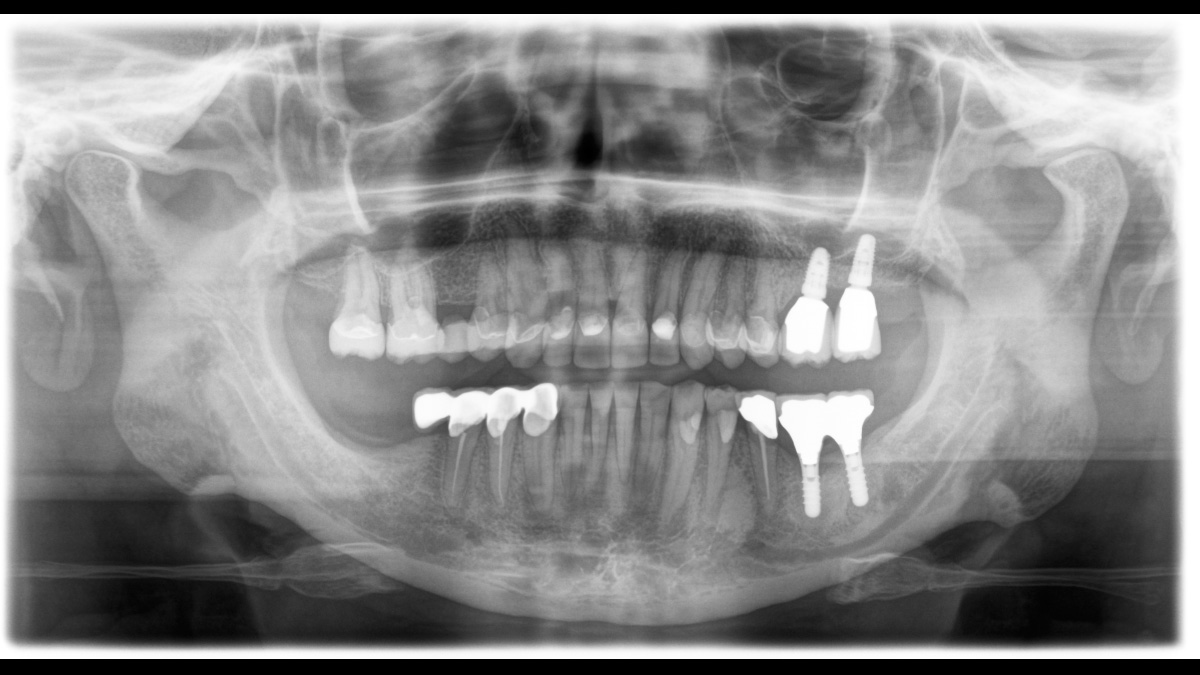

El equipo de radiología 2D/3D de alta calidad con una amplia gama de servicios para cada clínica. Ya sea como un dispositivo puramente 2D o como un módulo 3D, el Orthophos S es un socio confiable y está optimizado para las tareas diarias. Su sensor CsI Plus con función de autofoco garantiza imágenes claras, incluso en casos anatómicamente difíciles. El posicionamiento automático del paciente junto con el bloque de mordida oclusal patentado permite un posicionamiento del paciente fácil y que ahorra tiempo. Para su uso en ortodoncia, la Orthophos S también está disponible con un brazo cefalométrico opcional. Y como para Dentsply Sirona es importante estar preparado para el futuro, el brazo cefalométrico se puede reacondicionar en cualquier momento.

El enfoque correcto es crucial para excelentes radiografías panorámicas. Con la función de autofoco, usted recibirá automáticamente una imagen con la mejor nitidez posible en foco. Los dispositivos de radiología de Dentsply Sirona toman varios miles de imágenes individuales en un ciclo e identifican automáticamente las áreas donde la mandíbula está posicionada de manera óptima. Luego, sin ningún paso manual adicional, estas imágenes se muestran en una nítida imagen final.

El sistema detecta las áreas relevantes a partir de varios miles de imágenes individuales en un ciclo e identifica automáticamente las áreas donde la mandíbula está posicionada de manera óptima.

Imágenes nítidas.